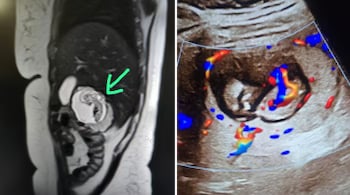

In a rare and shocking medical case, doctors in Bulandshahr, Uttar Pradesh, discovered a 12-week-old foetus developing in a woman's liver instead of the uterus during an MRI scan. The rare medical condition, known as intrahepatic ectopic pregnancy, is extremely rare and carries significant risks. Experts suggested that this could be the first such case ever reported in India, News18 reported.

“When I saw the scan, I could not believe my eyes. The foetus was embedded in the right lobe of the liver, and there were clear cardiac pulsations. I have never seen such a case in my career, and according to available data, this might be India’s first intrahepatic ectopic pregnancy," Dr KK Gupta, a radiologist at a private imaging centre in Meerut, who uncovered it while carrying out the MRI abdomen test of the 30-year-old woman, was quoted by News18 as saying.

According to Dr Gupta, the scan revealed a startling anomaly. “We observed a well-formed gestational sac inside the right lobe of the liver. The foetus measured approximately 12 weeks in gestational age. Most strikingly, the scan confirmed active cardiac pulsations, establishing that the foetus was alive. At the same time, the uterus was completely empty, ruling out a normal intrauterine pregnancy," Dr Gupta explained.

He further detailed that the foetus appeared embedded deep into the parenchymal tissue of the liver, with blood vessels from the organ supplying nutrition to the sac. This confirmed that the pregnancy had implanted directly into the hepatic tissue — an occurrence almost unheard of in India, the report added.

Dr Gupta also said that the diagnosis was double-checked by repeating certain MRI sequences to rule out imaging errors. “Initially, I even thought it might be an imaging artifact. But repeated scans, taken from different planes, confirmed the presence of a live foetus within the liver tissue itself. At that moment, we realised we were dealing with an extremely rare, high-risk pregnancy," he added.